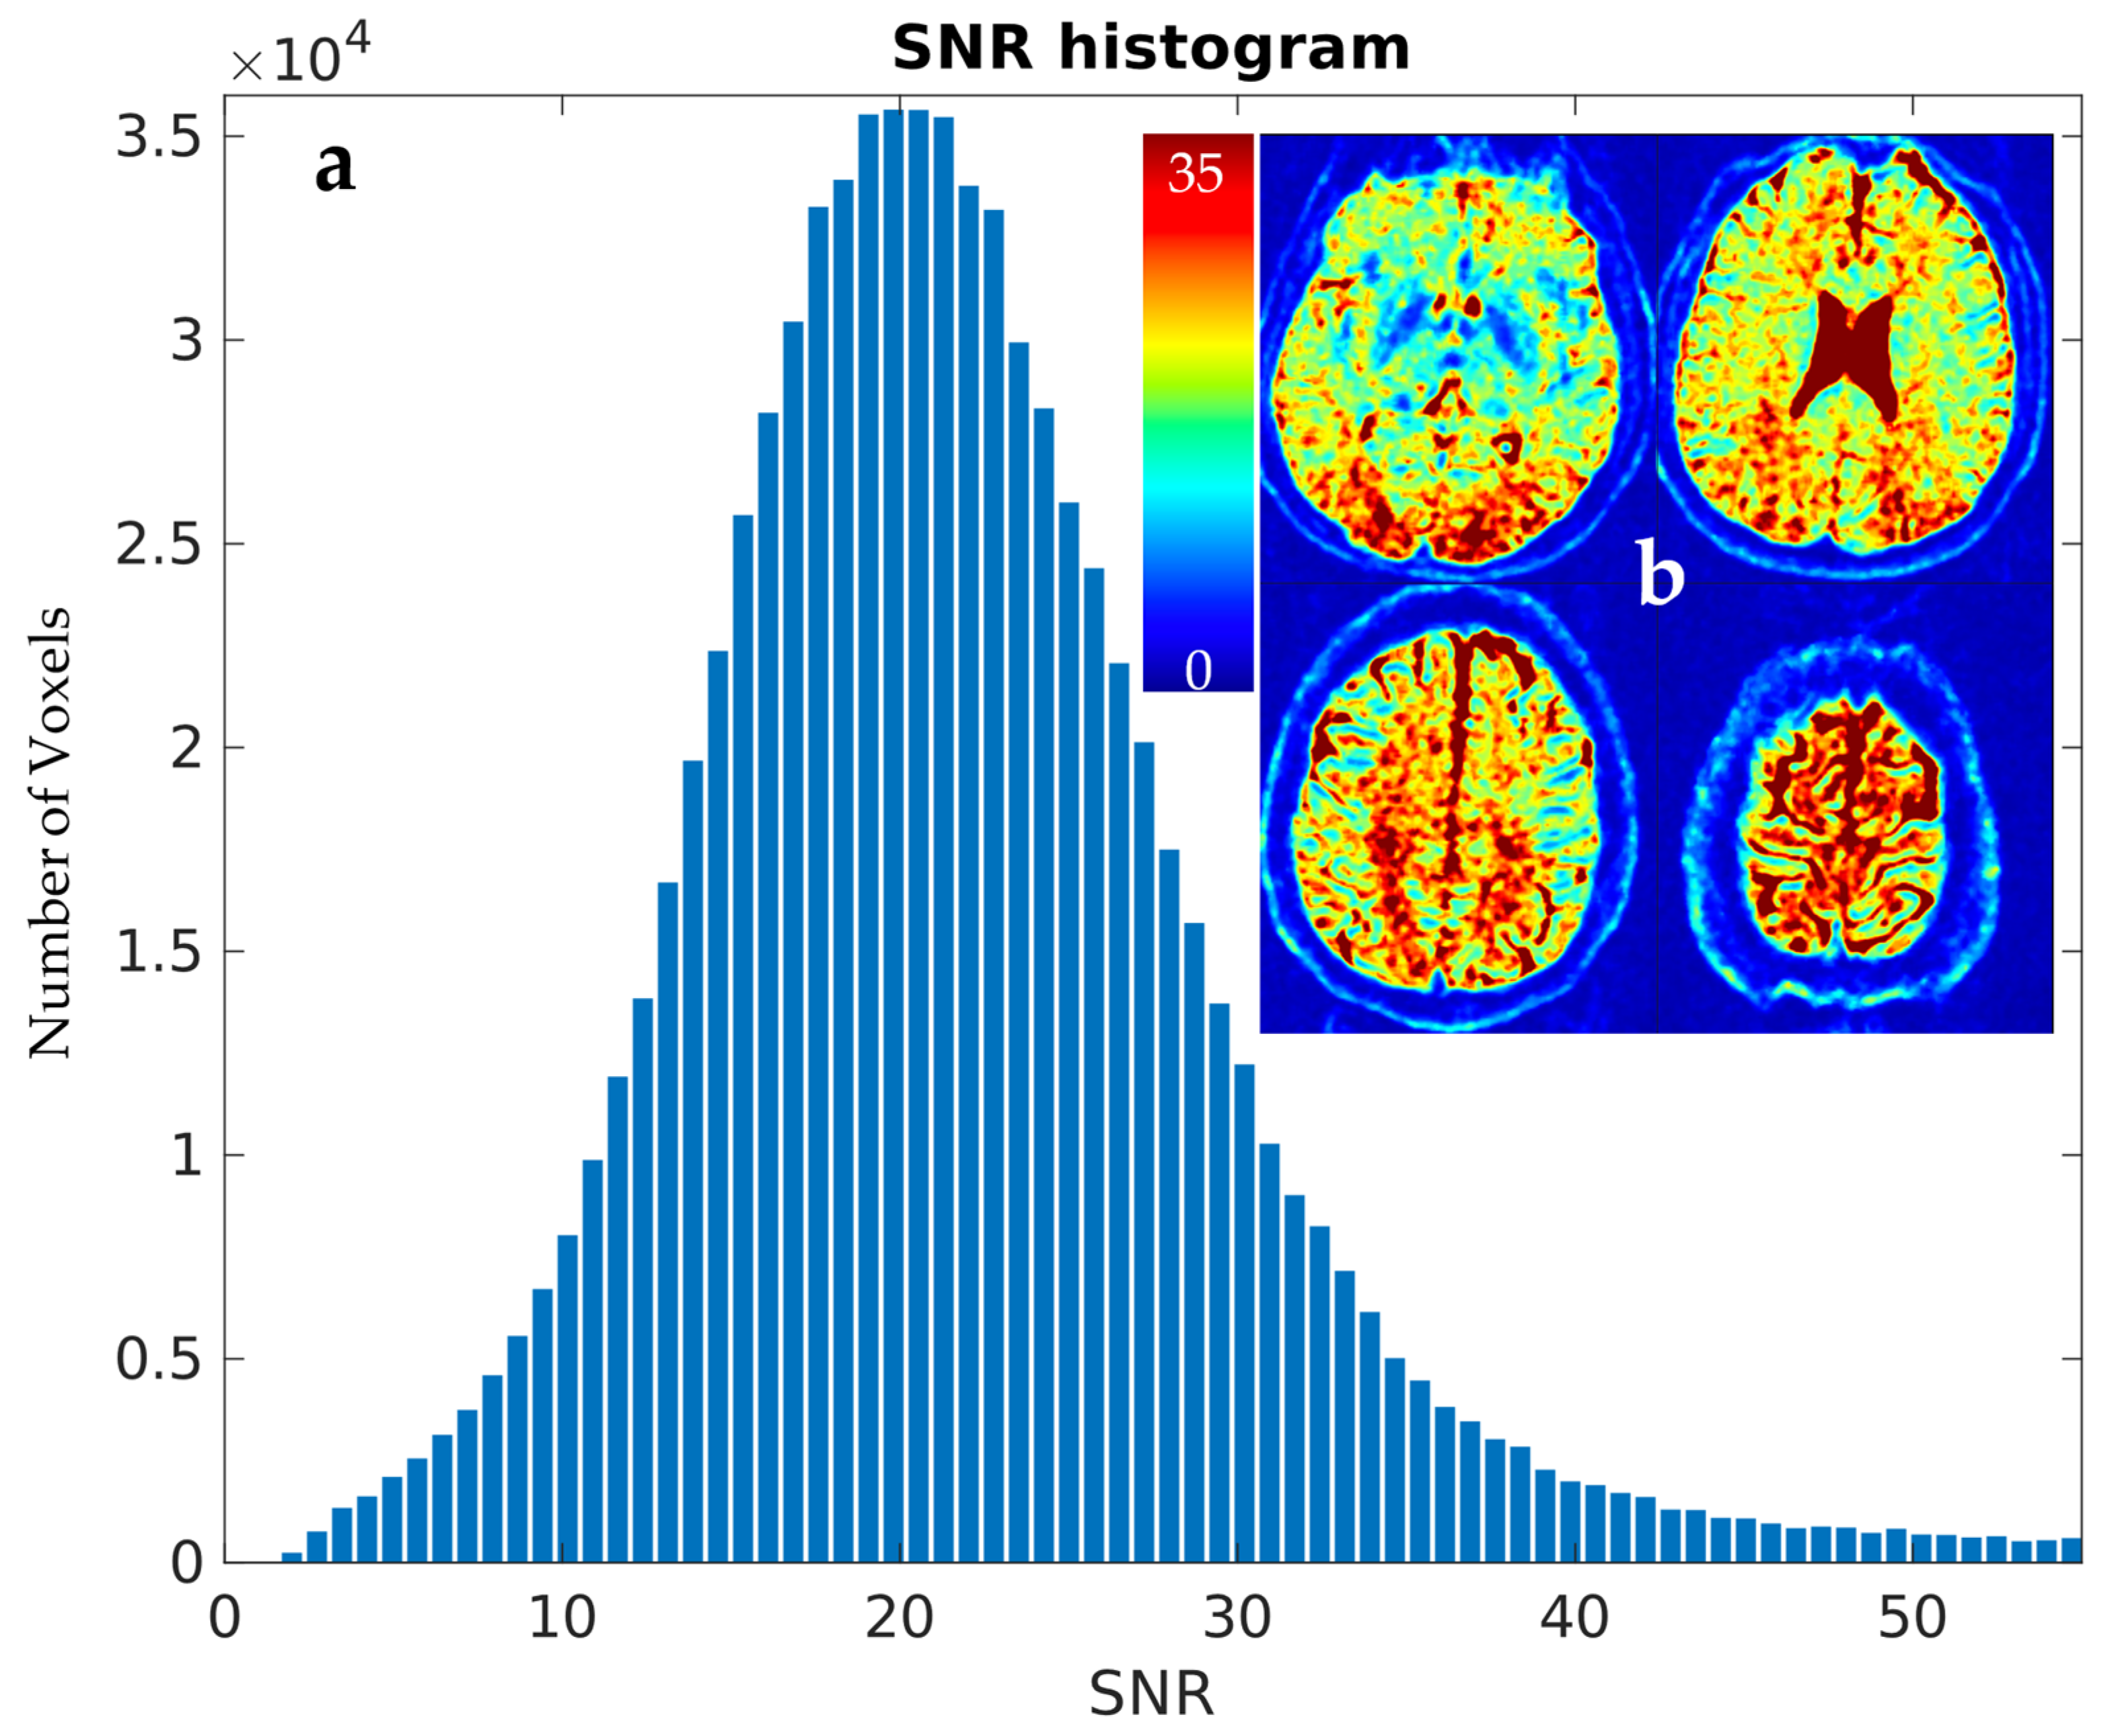

3.1. Estimation of Scanner-Specific SNR